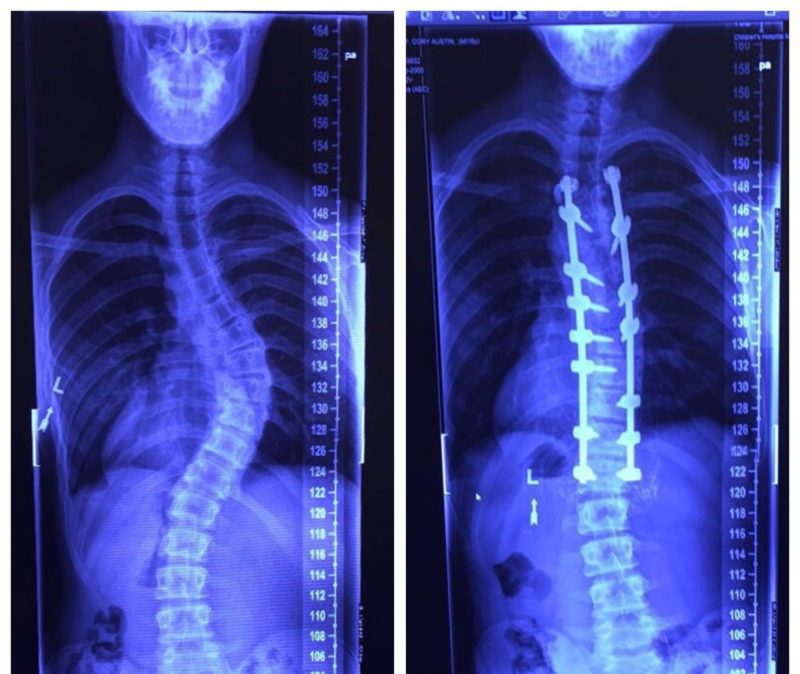

Research helps set standards in scoliosis surgical treatment

About 3% of adolescents have scoliosis ‒ a sideways curvature of the spine. While most instances are mild, some children suffer from more severe cases that worsen as they grow.

About 3% of adolescents have scoliosis – a sideways curvature of the spine. One of Dr. Ritzman’s investigations delves into innovative scoliosis correction procedures that require spinal rods.

One study focused on using computer modeling and biomechanical analysis for innovative scoliosis correction procedures that require spinal rods. The preliminary outcomes of this investigation are encouraging, prompting invitations to teach this method at national surgical courses and visiting professorships.